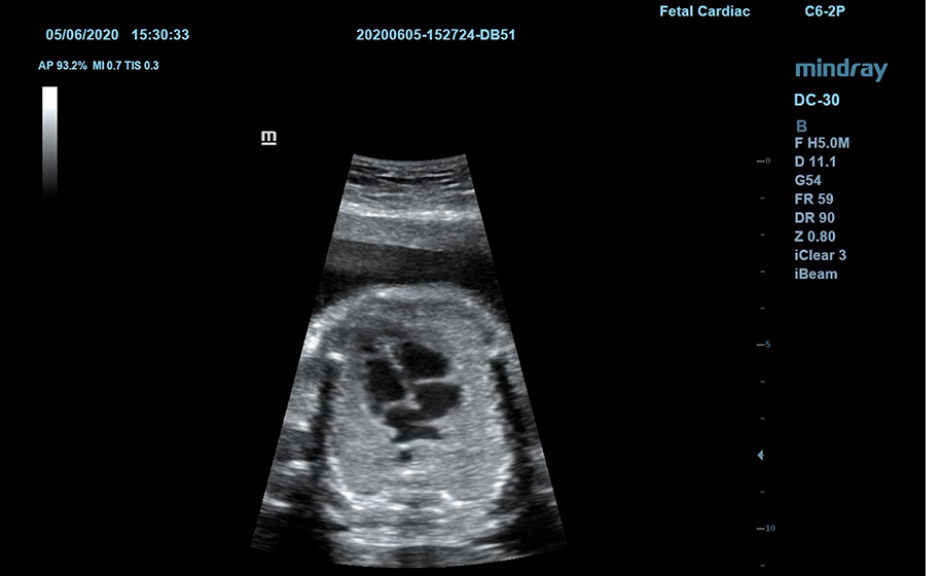

Normale anatomische illustraties met inbegrip van schematische beelden en ultrasoundbeelden.

Zijdelingse weergave van een standaard ultrasonogram dat visuele aanwijzingen geeft over de relevante gebieden.

Standaard ultrasoundbeelden

3

Vergelijking realtimescan ter referentie.